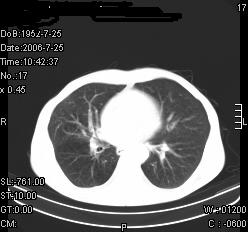

患者,男,54岁,咳嗦,咳痰20天。抗炎治疗2周。现esr76mm/h,目前患者症状明显好转,但发现两次ct片未见明显变化。两次分别做与7.25、7.31。第一次诊断右肺上叶炎症累计胸膜。大家看,从影像上内排除结核吗?

结核的可能性非常大,右上肺病变应该考虑干酪性肺炎。理由:

1.纵隔内多发淋巴结肿大。

2.esr76mm/h。

3.虽经抗炎治疗肺窗病灶有所吸收、减小,但纵隔窗病灶形态、密度、范围无明显变化。如果是单纯的大叶性肺炎,“抗炎治疗2周,目前患者症状明显好转”病灶应该基本消散了,至少也处于吸收消散期,密度变淡、范围变小。同时本病例所示其内的密度不均匀,见多发大小不一空洞样影也不符合大叶性肺炎吸收消散期表现。

病灶特点:片状 索条 结节混杂影,部分融合,密度不均,广泛累及相应胸膜.

临床治疗;二周未吸收.但症状好转.

多考虑:肺结核.